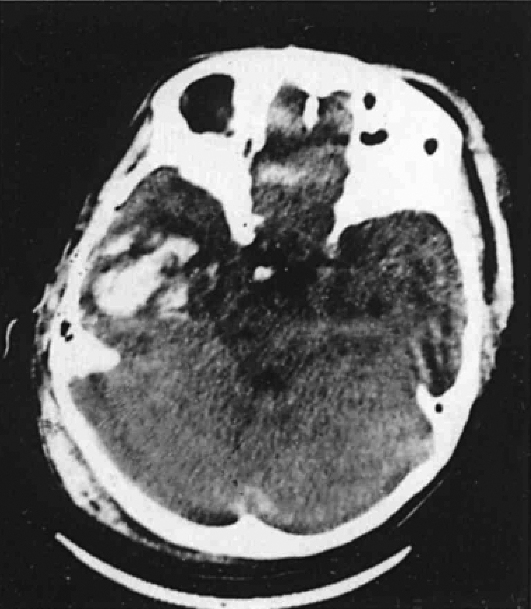

Контузия тяжелой степени

Контузия тяжелой степени 109 фото